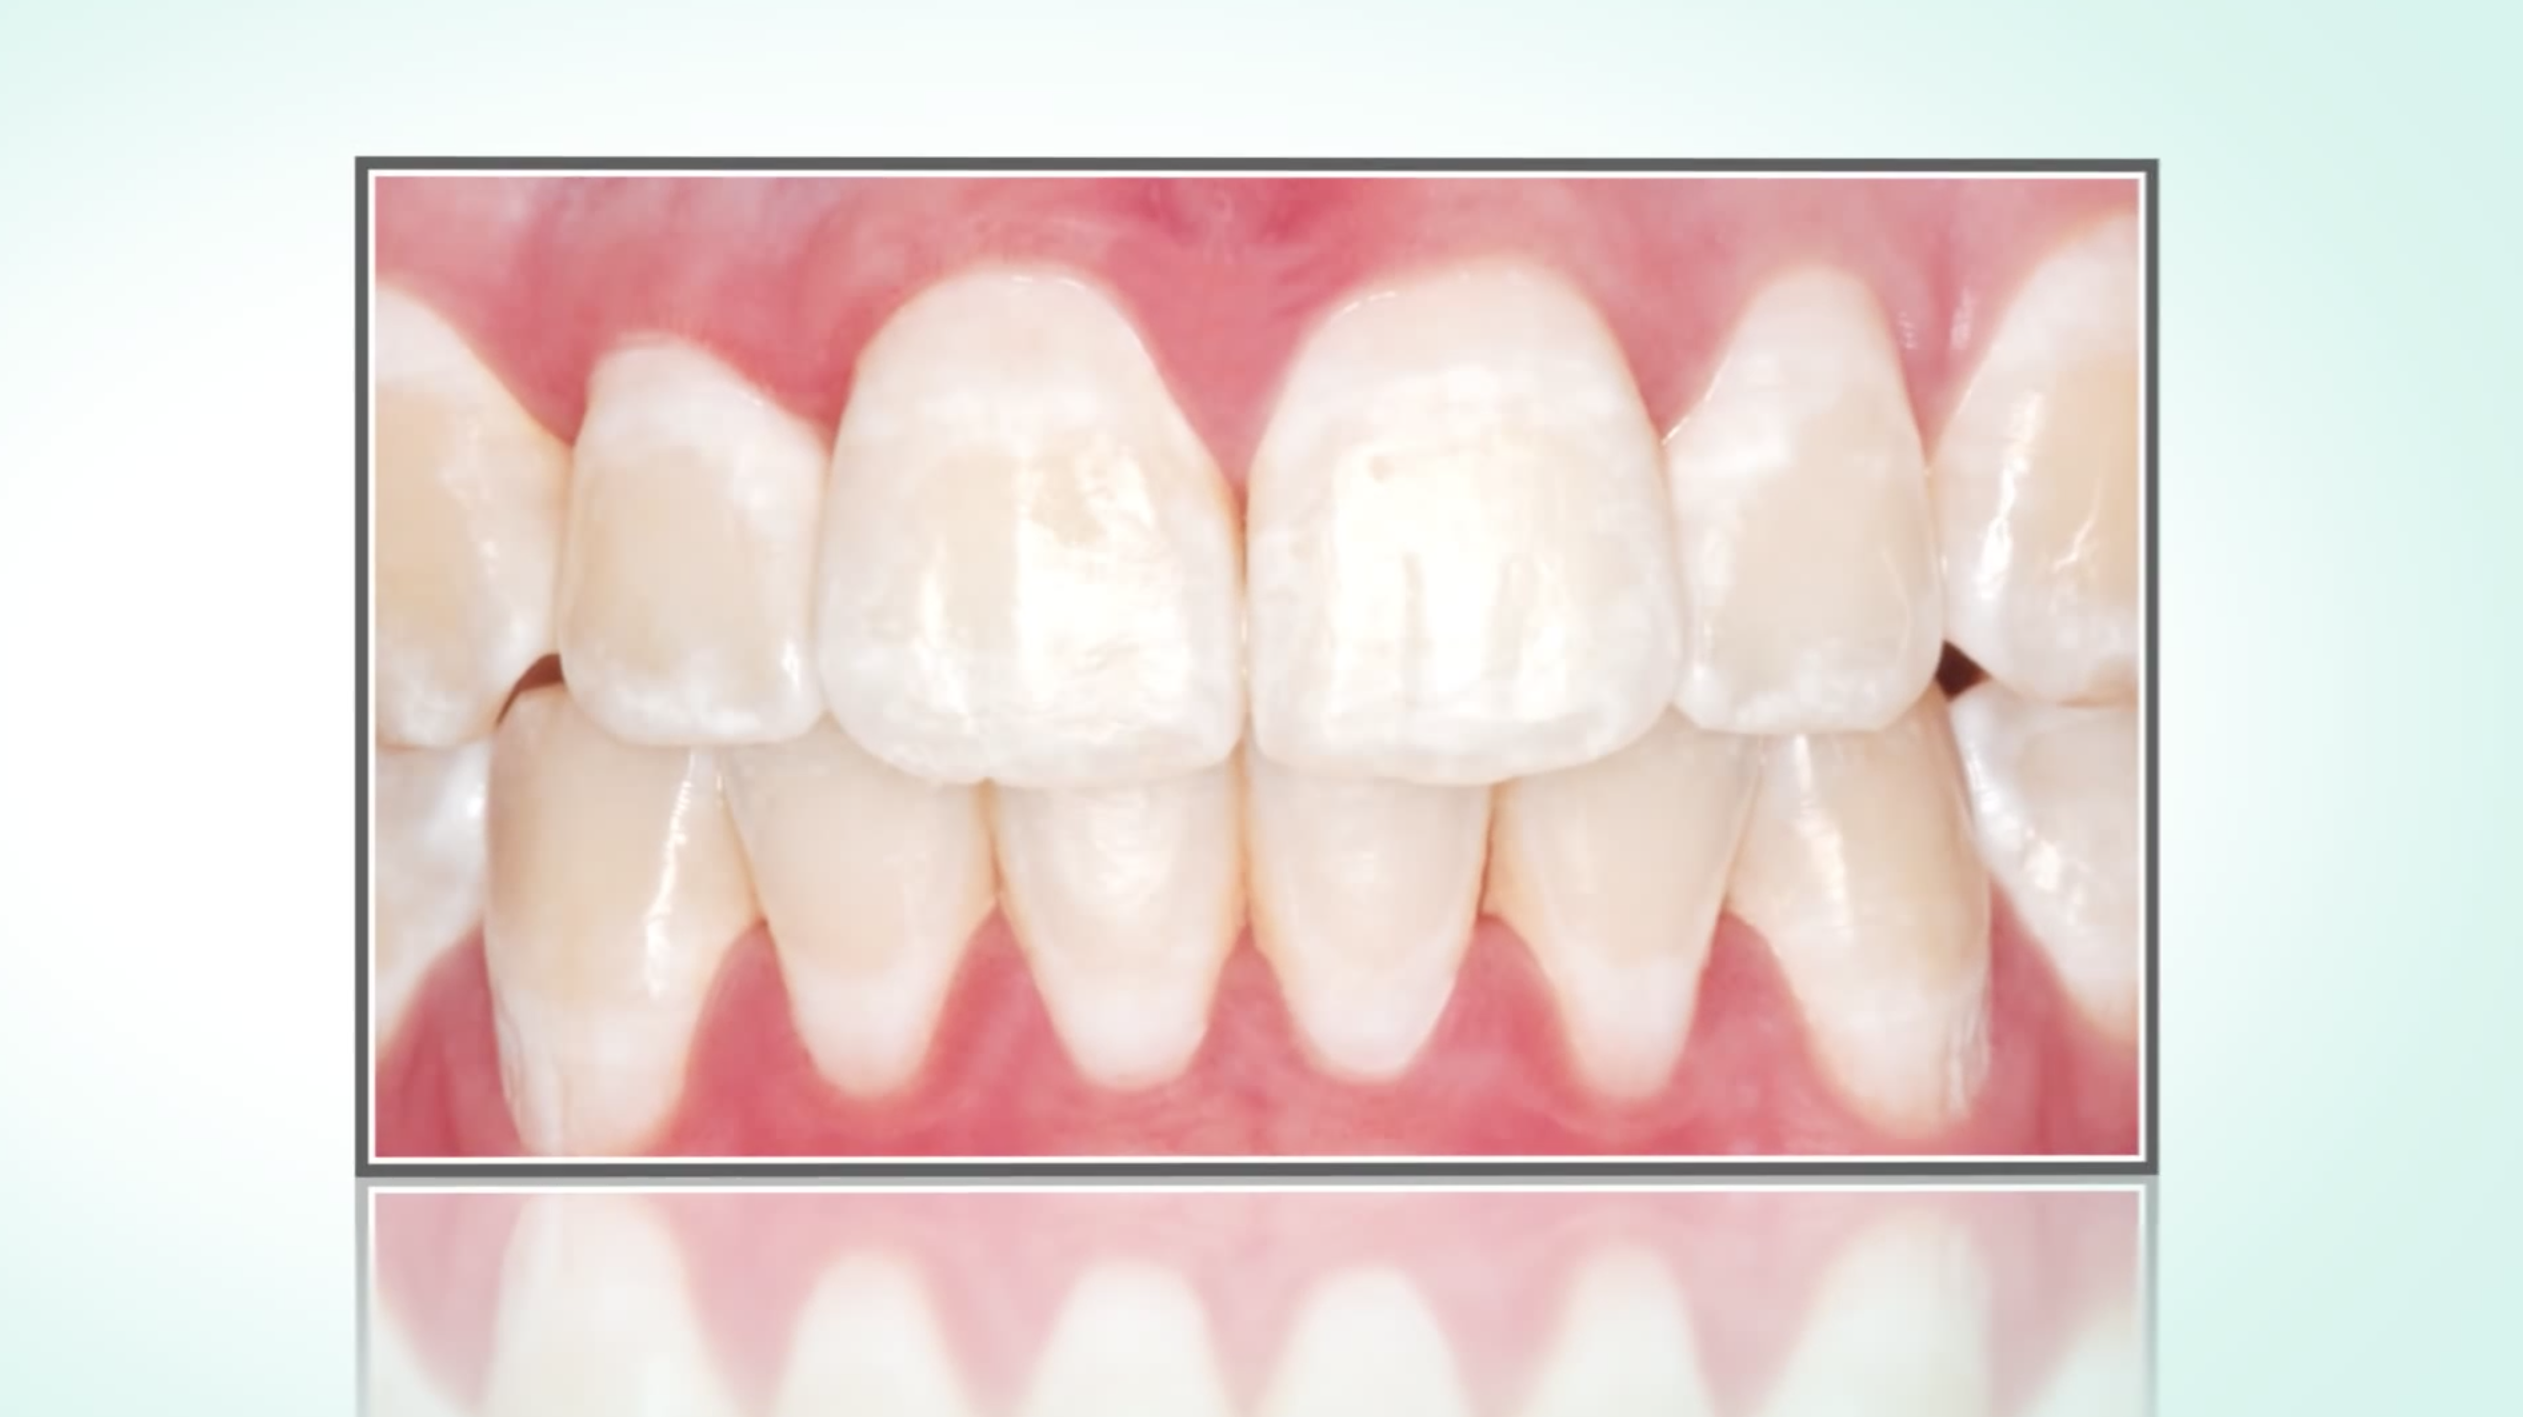

Was tun bei weißen Flecken auf den Zähnen (Fluorosen, nach Bracketentfernung, Initialkaries)?